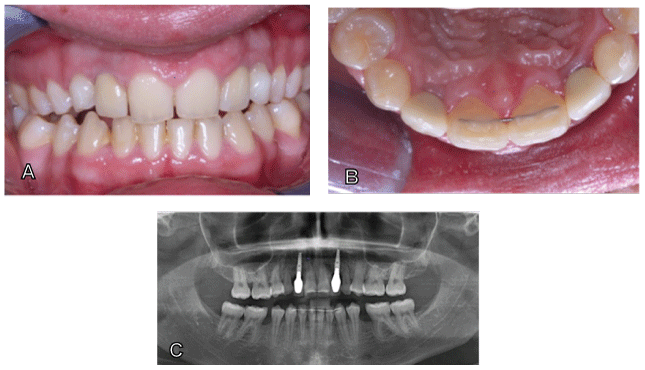

另外四年后,在21岁时,患者一旦她的原发性牙齿移植变得松动。此后患者迅速提供植入物。在促进松动的初级牙齿期间,只有含有骨置换材料的提取伤口(Bio-OSS,Fa。Geistlich,Baden-Baden,Germany),只能通过填充酶促措施进行轻微的肺泡措施。2.5月后,将植入物插入八周后(2×诺贝尔活性植入3.0×11.5,Zurich,Switzerland)和Prosthetics。图7显示了具有全陶瓷冠的植入物的假体护理后临床和X射线情况。可以实现高效的咬合饲养(图7A),与植入物周围的区域的美学上令人愉悦的柱状导致相关联(图7A和B)。OPG显示稳定的嵴骨状况(图7C)。位置35和45中的剩余较小的间隙被患者被患者出现问题。根据要求建议这些差距中的假体措施,因为这些间隙对于植入物太小。

图7:临床和X射线调查结果11年后21岁的患者。

A.面部观点

B.咬合视图,透露后正畸咬伤后令人愉悦的临床情况。

C.已经取出了初级移植物并被内塞植入物取代,而无需精细化骨增强程序。